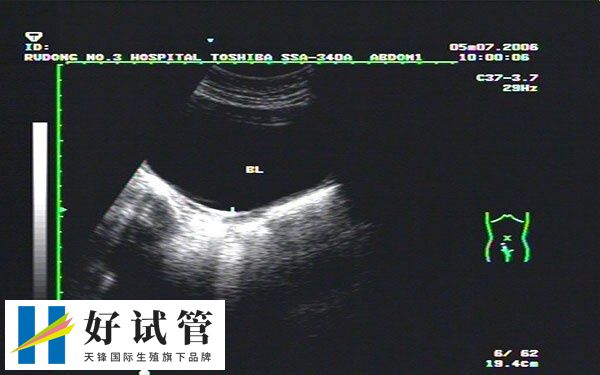

2、根据超声检查结果

超声检查可以确定受精卵的发育情况和大小,从而确定怀孕周数和预产期。通常在孕早期进行第一次超声检查,这时候可以看到胎儿的心跳。根据胎儿大小和发育情况来确定怀孕周数和预产期。